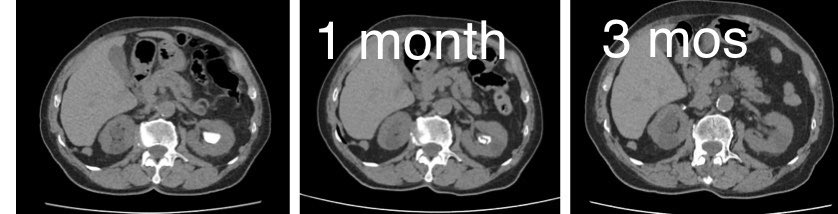

The best success 4 #endourologist:dissolving a big stone in 3 mos of alcalinisation in an octogenarian pt already scheduled for #PCNL elsewhere Always check HU on CT: all stones r white but below 500HU they r #uratic and dissolution is possibile & must b attempted before surgery!